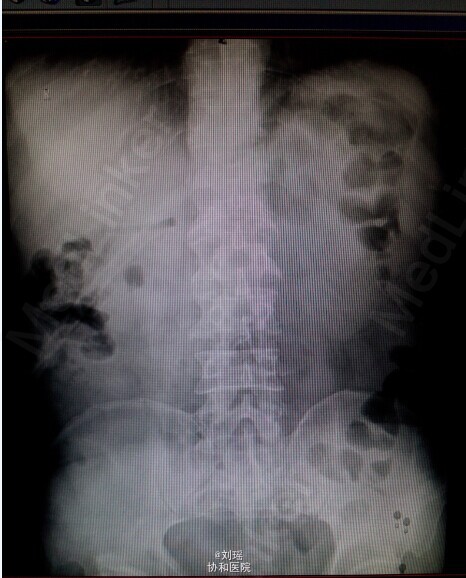

查体:生命体征平稳,慢性病容,皮肤巩膜重度黄染,右上腹T管,余无特殊。 辅助检查: 肝胆脾CT:右肾囊肿;胆总管粘液腺癌术后 T管造影:胆总管全段可见不同程度,不同大小之充盈缺损并不同程度狭窄,考虑为占位性病变。肝内胆管明显扩张。